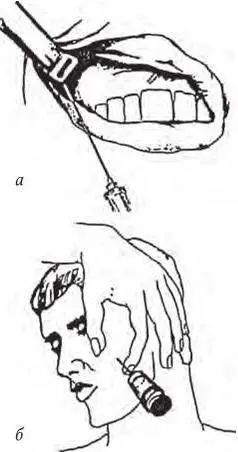

Рис . 1. Анестезия на бугре верхней челюсти:

а – внутриротовой доступ; б – внеротовой доступ

Анестезия на бугре верхней челюсти. Цель анестезии – блокирование задних альвеолярных ветвей, располагающихся в крылонебной ямке и на задненаружной поверхности бугра челюсти. Этот вид анестезии может быть выполнен внутриротовым и внеротовым доступами.

Внутриротовой доступ : при полуоткрытом рте зубоврачебным зеркалом отводят в сторону щеку, обеспечивая достаточный обзор свода преддверия рта и натяжение слизистой оболочки переходной складки в области моляров. Иглу вкалывают в слизистую оболочку выше проекции верхушек зубов на уровне второго-третьего моляров, а при их отсутствии – позади скулоальвеолярного гребня, вводя ее под углом 45° и продвигая вверх, назад и внутрь. При этом нужно следить за тем, чтобы игла все время скользила скошенной поверхностью острия по кости. По ходу продвижения иглы следует медленно выпускать раствор анестетика, предупреждая тем самым повреждение кровеносных сосудов крыловидного сплетения. Продвигая иглу на глубину 2 – 2,5 см, депонируют раствор анестезирующего вещества, чем достигается обезболивание области моляров, прилежащих к ним со стороны преддверия рта слизистой оболочки и надкостницы, а также задненаружной костной стенки верхнечелюстной пазухи (рис. 1, а ).

Внеротовой доступ : проколов кожу у передненижнего угла скуловой кости, направляют иглу под углом 45° вверх и внутрь к бугру верхней челюсти, доводя ее до кости; после чего депонируют раствор анестетика. Время наступления анестезии в зоне обезболивания такое же, как и при анестезии внутриротовым доступом (рис. 1, б ).